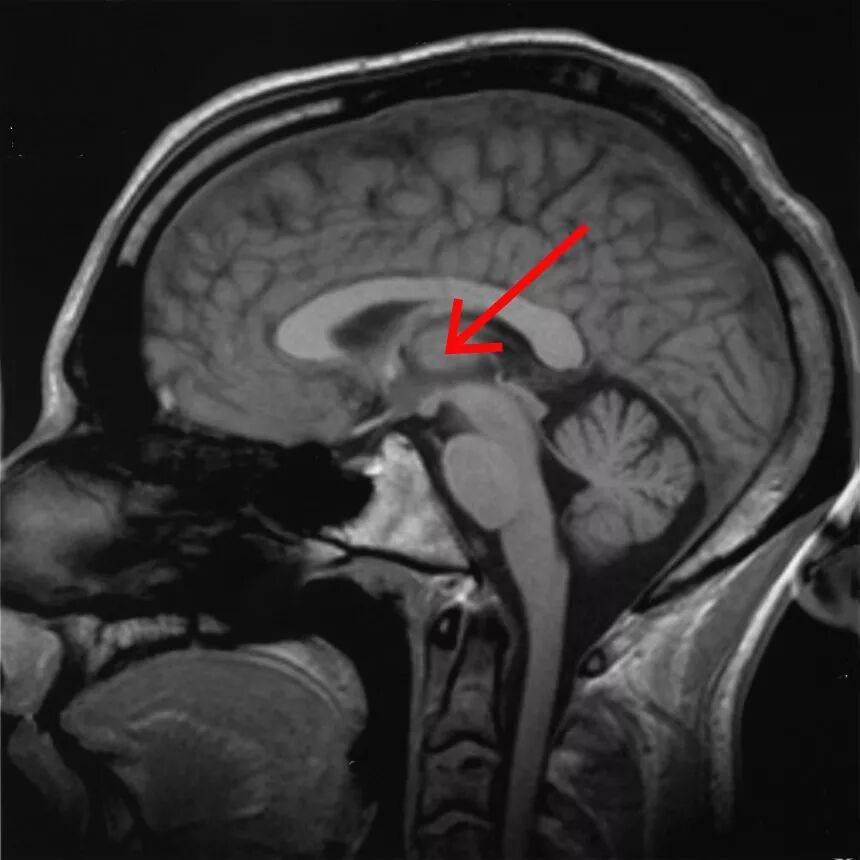

人脑的矢状切面,丘脑的位置通过红色箭头标出。图源:wikipedia

因此,幻听不仅仅告诉了我们人类的感知系统是如何运行的,也向我们表明丘脑——也就是莎拉因肿瘤受到损伤的部位,在听觉处理过程中起到了基础和先导的作用。在我们把听到的信息传递到其他大脑区域进行解读之前,丘脑就已经起了作用。我们看到的和听到的周围信息首先传入丘脑——我们可以把丘脑想象成一个中继站,对我们看到和听到的信息进行分类分路,再输送到适当的皮层进行整理。